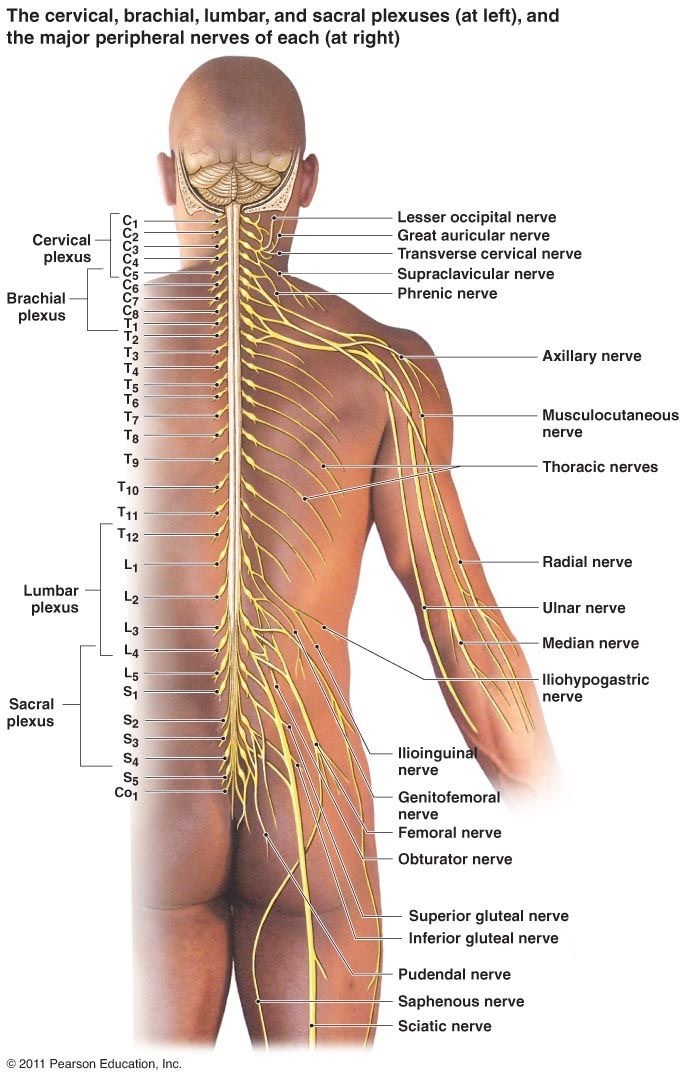

昨年の10月から週に1回のペースでアジャストメントを行ってきました。アジャストメントを行った箇所は、骨盤(腸骨や仙骨)、第6胸椎(T6)から第9胸椎(T9)、第7頚椎(C7)が中心でした。

脊柱解剖学(Spinal Anatomy)

脊柱解剖学(Spinal Anatomy)